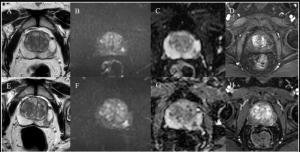

Nine Takeaways from New Review of PSMA PET/CT and Whole-Body MRI for Advanced Prostate Cancer

Researchers found no statistically significant differences between bpMRI and mpMRI evaluations of patients with PI-RADS 3 presentations, according to a new multi-reader study.

Catch up on the most-well viewed prostate cancer imaging content in October 2025.